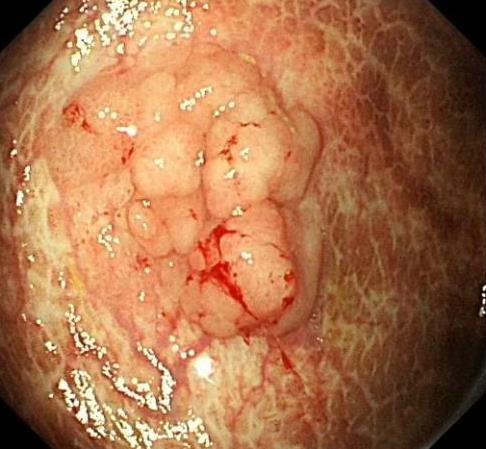

• 色素内镜和窄带成像技术联合放大内镜对早期结直肠癌及癌前病变的诊断价值研究

2026, 32(1):35-41. DOI: 10.12235/E20250020

摘要 (92) HTML (29) PDF 5.33 M (93) 评论 (0) 收藏

摘要:目的 探究色素内镜(CE)和窄带成像技术(NBI)联合放大内镜(ME)对早期结直肠癌及癌前病变的诊断价值研究。方法 选取2023年8月-2024年7月于该院接受检查的疑似早期结直肠癌及癌前病变的患者160例。采用四格表法,分析NBI-ME和CE-ME检测早期结直肠癌及癌前病变的敏感度、特异度和准确度;采用Kappa一致性检验,分析CE-ME和NBI-ME诊断早期结直肠癌及癌前病变与病理检查的一致性。结果 病理结果显示,良性病变52例,癌前病变90例,结直肠癌18例。CE-ME检测结果显示,良性病变43例,癌前病变101例,结直肠癌16例,漏诊率为33.33%;CE-ME诊断早期结直肠癌及癌前病变与病理检查的一致性中度(Kappa = 0.605,P < 0.01),敏感度为66.67%,特异度为97.18%,准确度为93.75%。NBI-ME检查结果显示,良性病变43例,癌前病变100例,结直肠癌17例,漏诊率为16.67%,NBI-ME诊断早期结直肠癌及癌前病变与病理检查的一致性较高(Kappa = 0.714,P < 0.01),敏感度为88.33%,特异度为98.59%,准确度为96.88%。CE-ME与NBI-ME两者联合检查结果显示,良性病变56例,癌前病变86例,结直肠癌18例,漏诊率为5.56%,两者联合诊断早期结直肠癌及癌前病变与病理检查的一致性极高(Kappa = 0.857,P < 0.01),敏感度为94.44%,特异度为99.30%,准确度为98.75%,高于CE-ME和NBI-ME单独检查。结论 CE和NBI联合ME对早期结直肠癌及癌前病变具有较高的诊断价值。值得应用于临床。